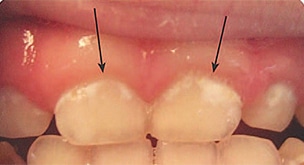

Severe ECC (S-ECC) is defined as any sign of smooth-surface caries in children younger than age 3. Additionally, in children ages 3 through 5, one or more dmf surfaces in primary maxillary anterior teeth, or a dmf score of ≥ 4 (age 3), ≥ 5 (age 4), or ≥ 6 (age 5) surfaces also constitutes S-ECC.3 The typical early sign of ECC is the crescent shaped white spot lesion at the gingival margin (Figure 1 to Figure 4).